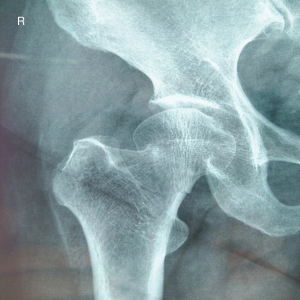

The patient was a 63-year-old male worker, previously fit and well, who fell and hurt himself by accident. He felt severe pain in his left hip and was sent to Affiliated Hospital of Shandong University of Traditional Chinese Medicine immediately. We found external rotation deformity of his left limb and performed an X-ray examination. Unfortunately, we found a left femoral neck fracture (Garden Index III) (Figure 2). Due to the significant displacement, the patient was treated surgically with closed reduction and percutaneous internal fixation using three parallel cannulated screws placed in an inverted triangle configuration. The three guide pins were inserted (Figure 3) into the three guide pin insertion points (C1, C2, and C3) that had been located with our localization method (Figure 4). Then three parallel cannulated screws were implanted to fix the fracture (Figure 5). Postoperative follow-up was performed periodically over 12 months to evaluate the hip function and observe complications. Overall, we achieved a satisfactory therapeutic outcome without complications (Figure 6).